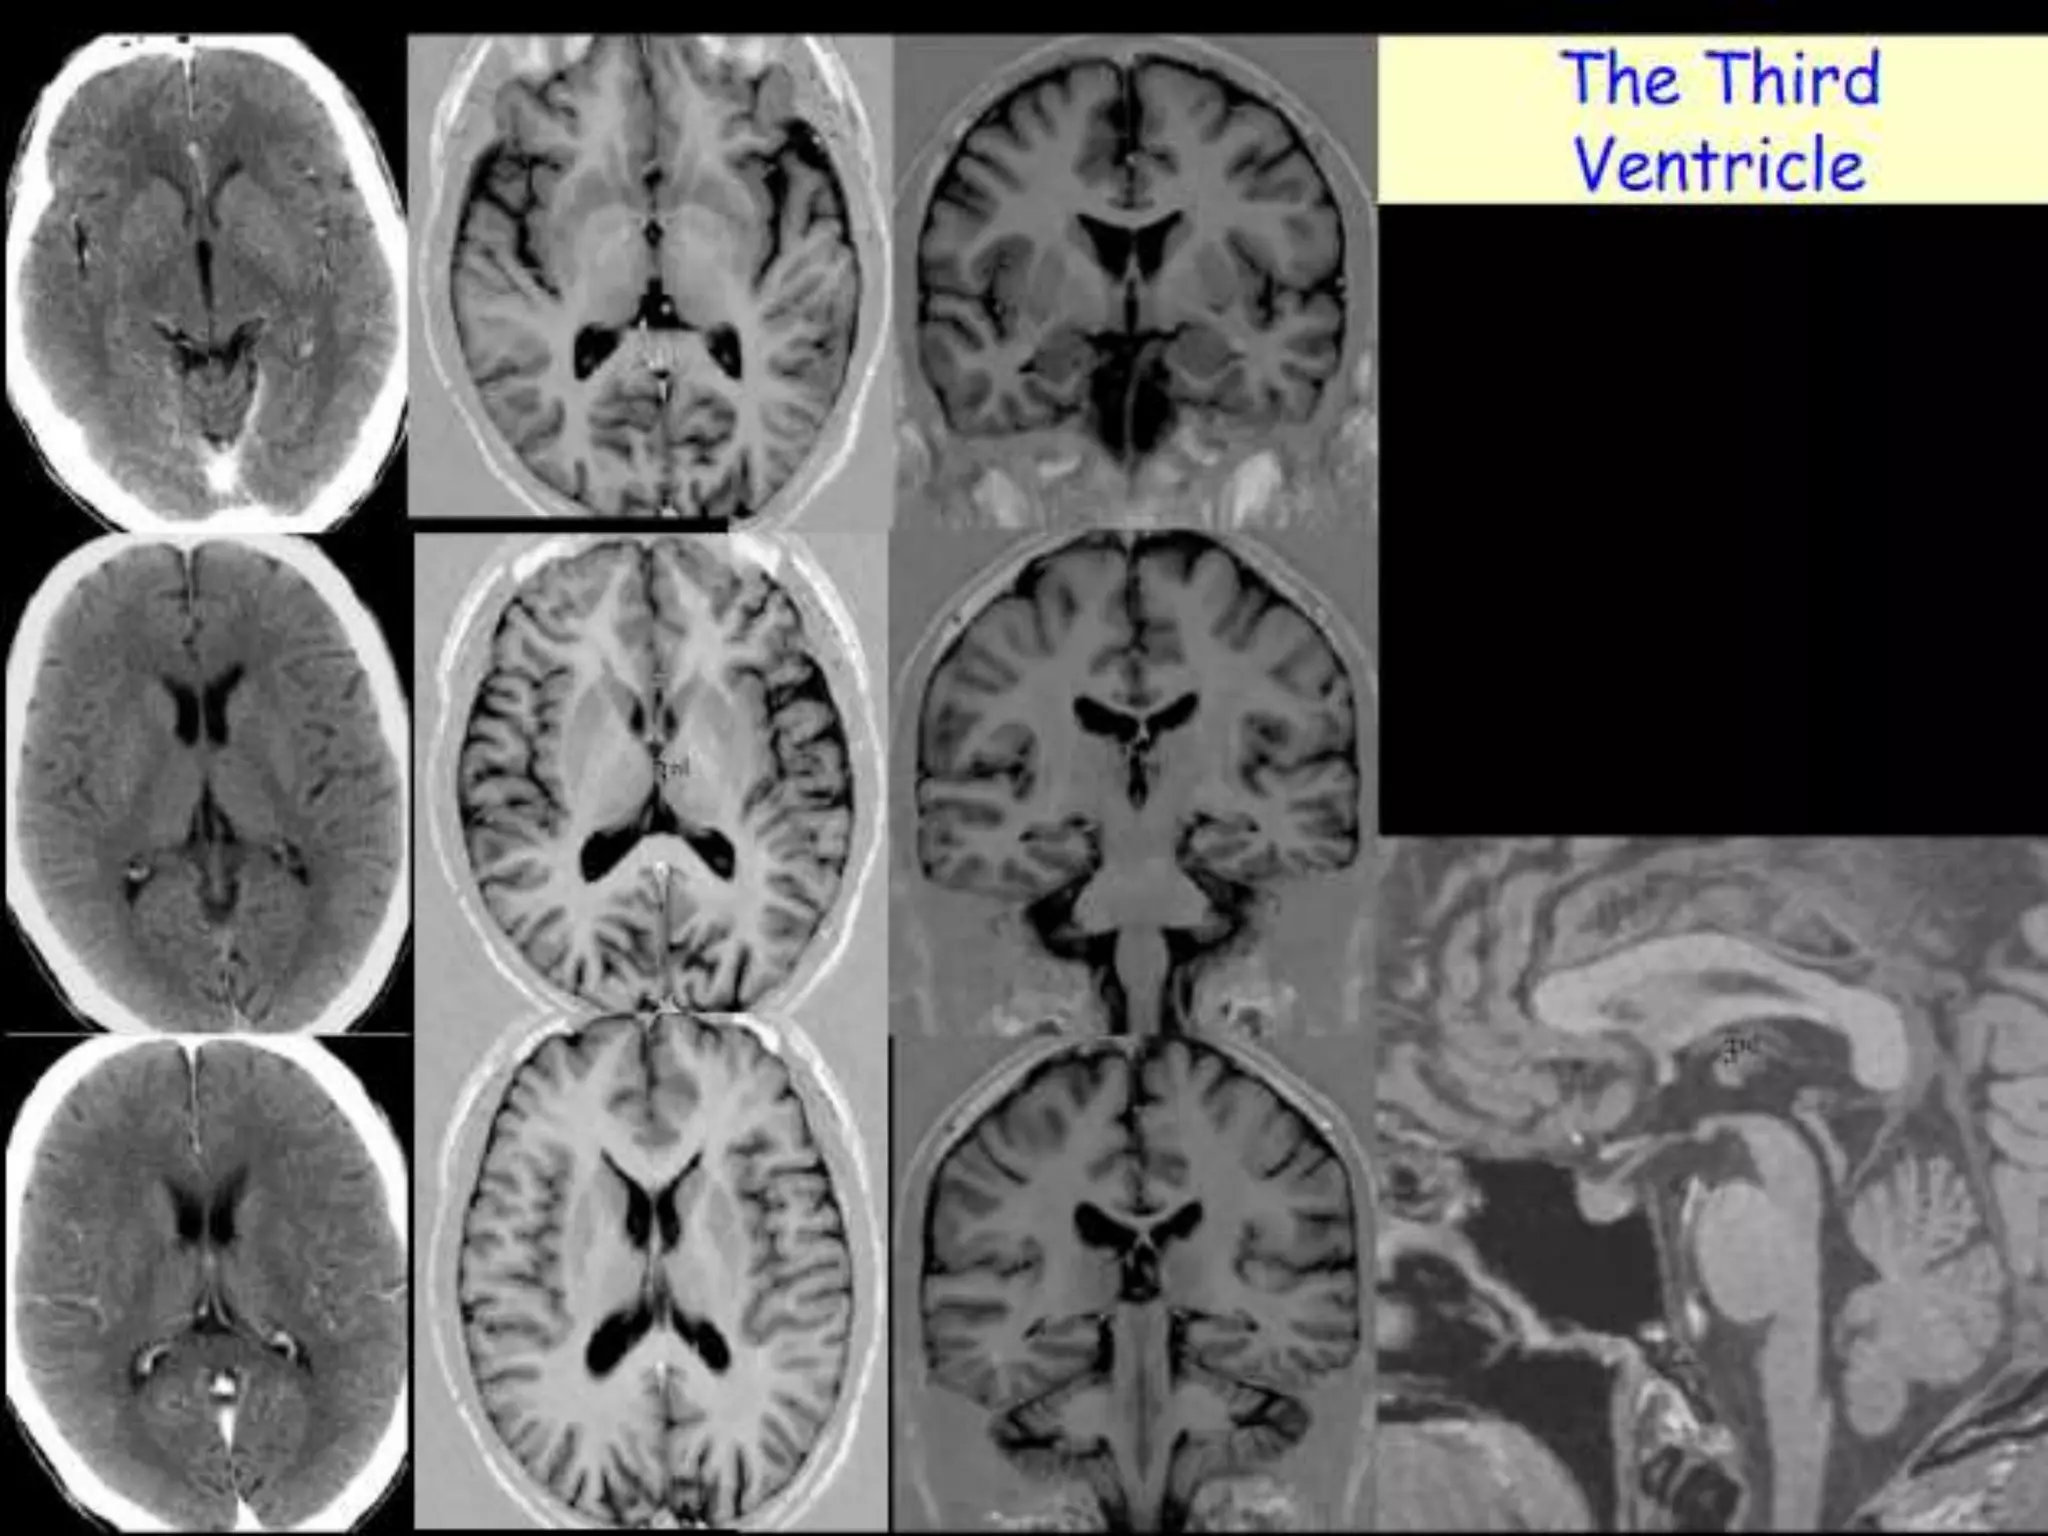

The third ventricle is a slit like ventricle midline cavity of

the diencephalons. It communicates with the lateral ventricles

via the interventricular foramina of Monro and with the fourth

ventricle via the cerebral aqueduct. It contains choroid plexus

in its roof.

• 14.

The third ventricleis a slit like ventricle midline cavity of the diencephalons. It communicates with the lateral ventricles via the interventricular foramina of Monro and with the fourth ventricle via the cerebral aqueduct. It contains choroid plexus in its roof. The fourth ventricle is a rhomboid-shaped cavity overlying the pons and medulla, extending from the central canal of the upper cervical spinal cord to the cerebral aqueduct of the midbrain. There is a small lateral recess on each side of the fourth ventricle, which contains choroid plexus that protrudes through the foramina of Luschka into the subarachnoid space. A small median aperture in the caudal part of the ventricle is known as the foramen of Magendie. Via the two lateral foramina of Luschka and the single medial foramen of Magendie, CSF flows into the ventricular system into the subarachnoid spaces.